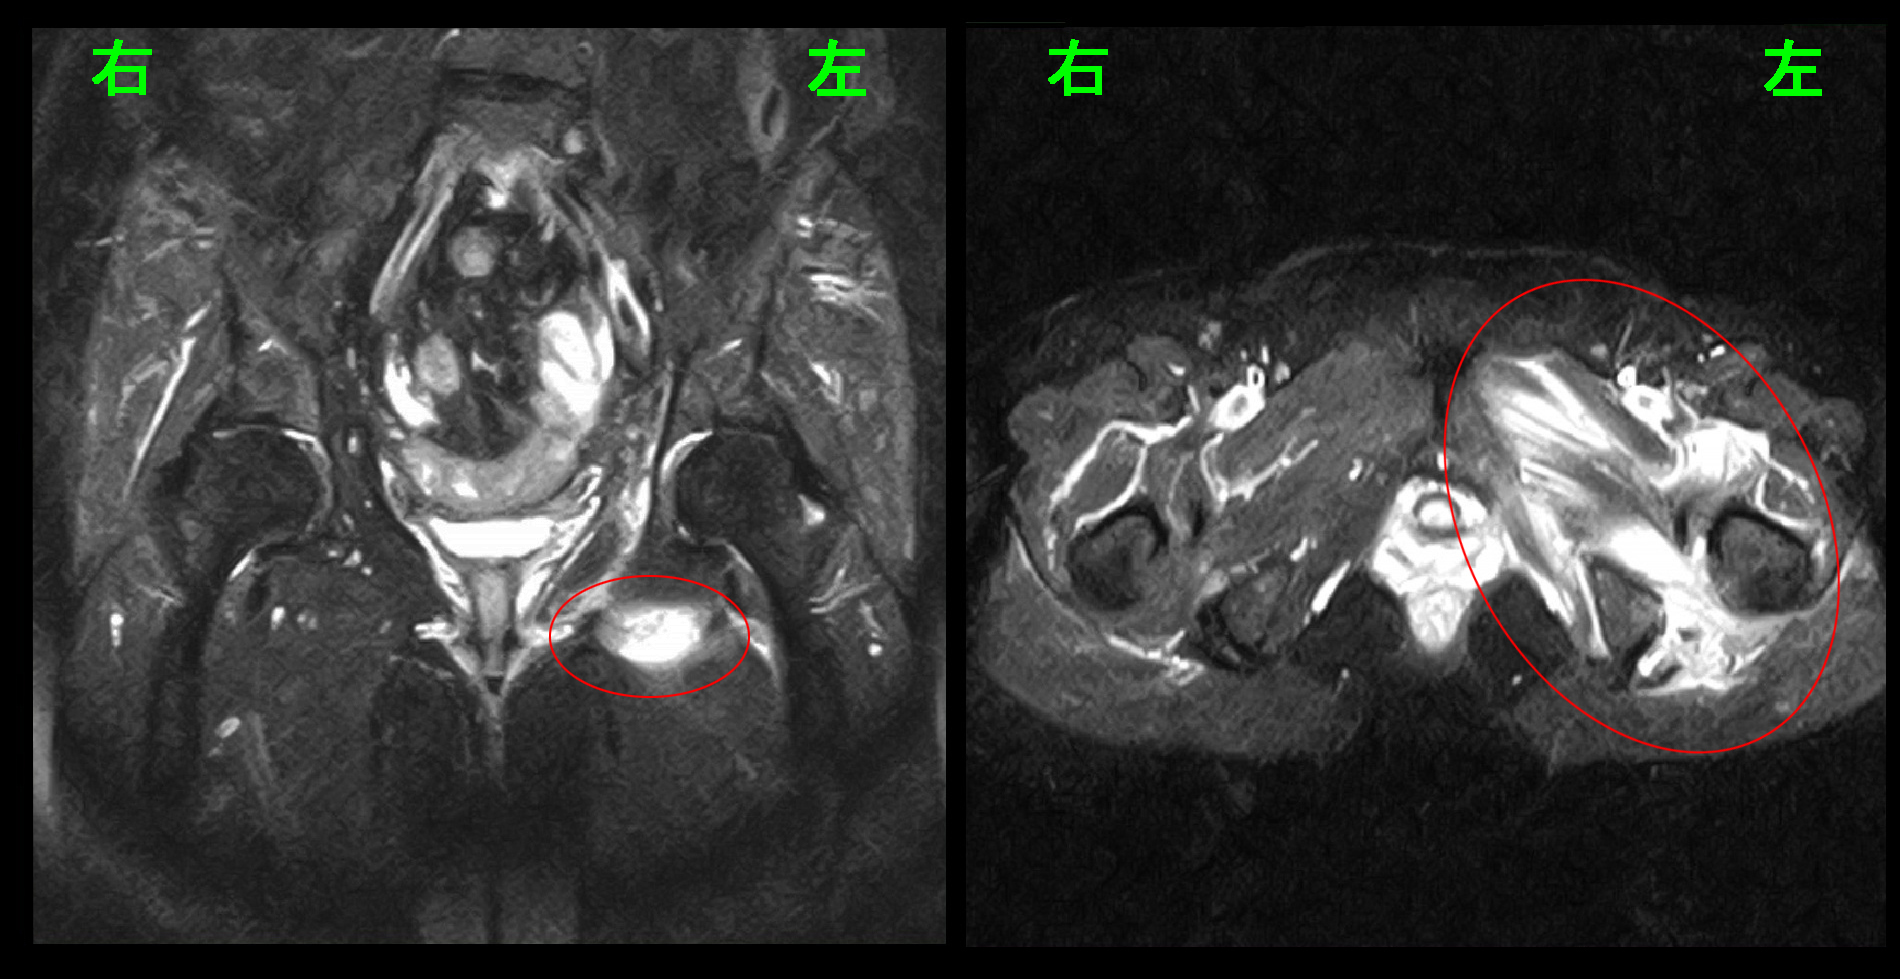

65才女 MR2.jpg腰椎のMRI検査の所見は変わりはありませんでしたが、股関節のMRI検査で左股関節周囲に広範な肉離れの所見(筋肉層の中に出血を示す白い所見)が確認されました。患者さんが10か月前と同じ腰に起因する痛みと感じても、その原因は全く別なものでした。